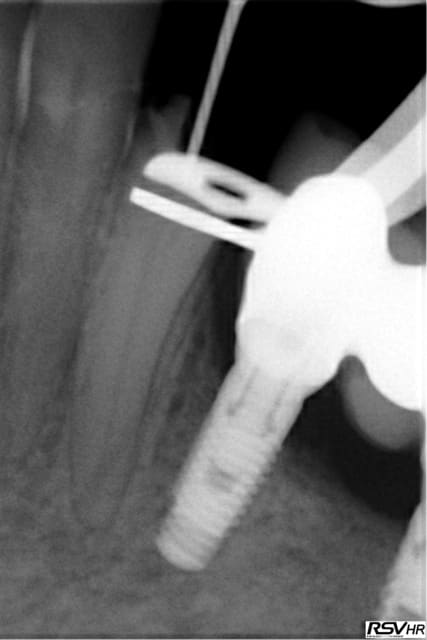

J'utilise le système heroshaper+digue+hypo+condensation

Mac Spadden(thermomécanique)

J'ai posté des radios biopulpectomies et retraitements

canalaires précédemment.

L'obturation 3D est indispensable pour un traitement hermétique.Mon associé utilise le système protaper et

effectivement cela élargit plus.Sur ces 7 dernières années

j'obtiens de bons résultats;mon avis le système heroshaper

casse moins mais n'hésite pas à jeter un heroshaper

même si non déspiralé ;si il a travaillé un peu en force

ou si la morphologie canalaire est un peu compliquée ou courbe;on fait un peu un usage unique pour éviter tout

problème plus tard!(quelque soit le système)on récapitule

avec un instrument à mains;pour une bonne herméticité

le système Mac spadden est le plus efficace ,utlisé par des endos exclusifs,et le moins cher (un cone de gutta est suffisant)Ma séquence classique instrument à main N10

héroshaper N20 6%/4% N25 4% N30 4% MAC SPADDEN un cone de gutta/ciment sealite régular

J'ai reposté quelques radios de biopulpectomies

RTE dans un précédent post...